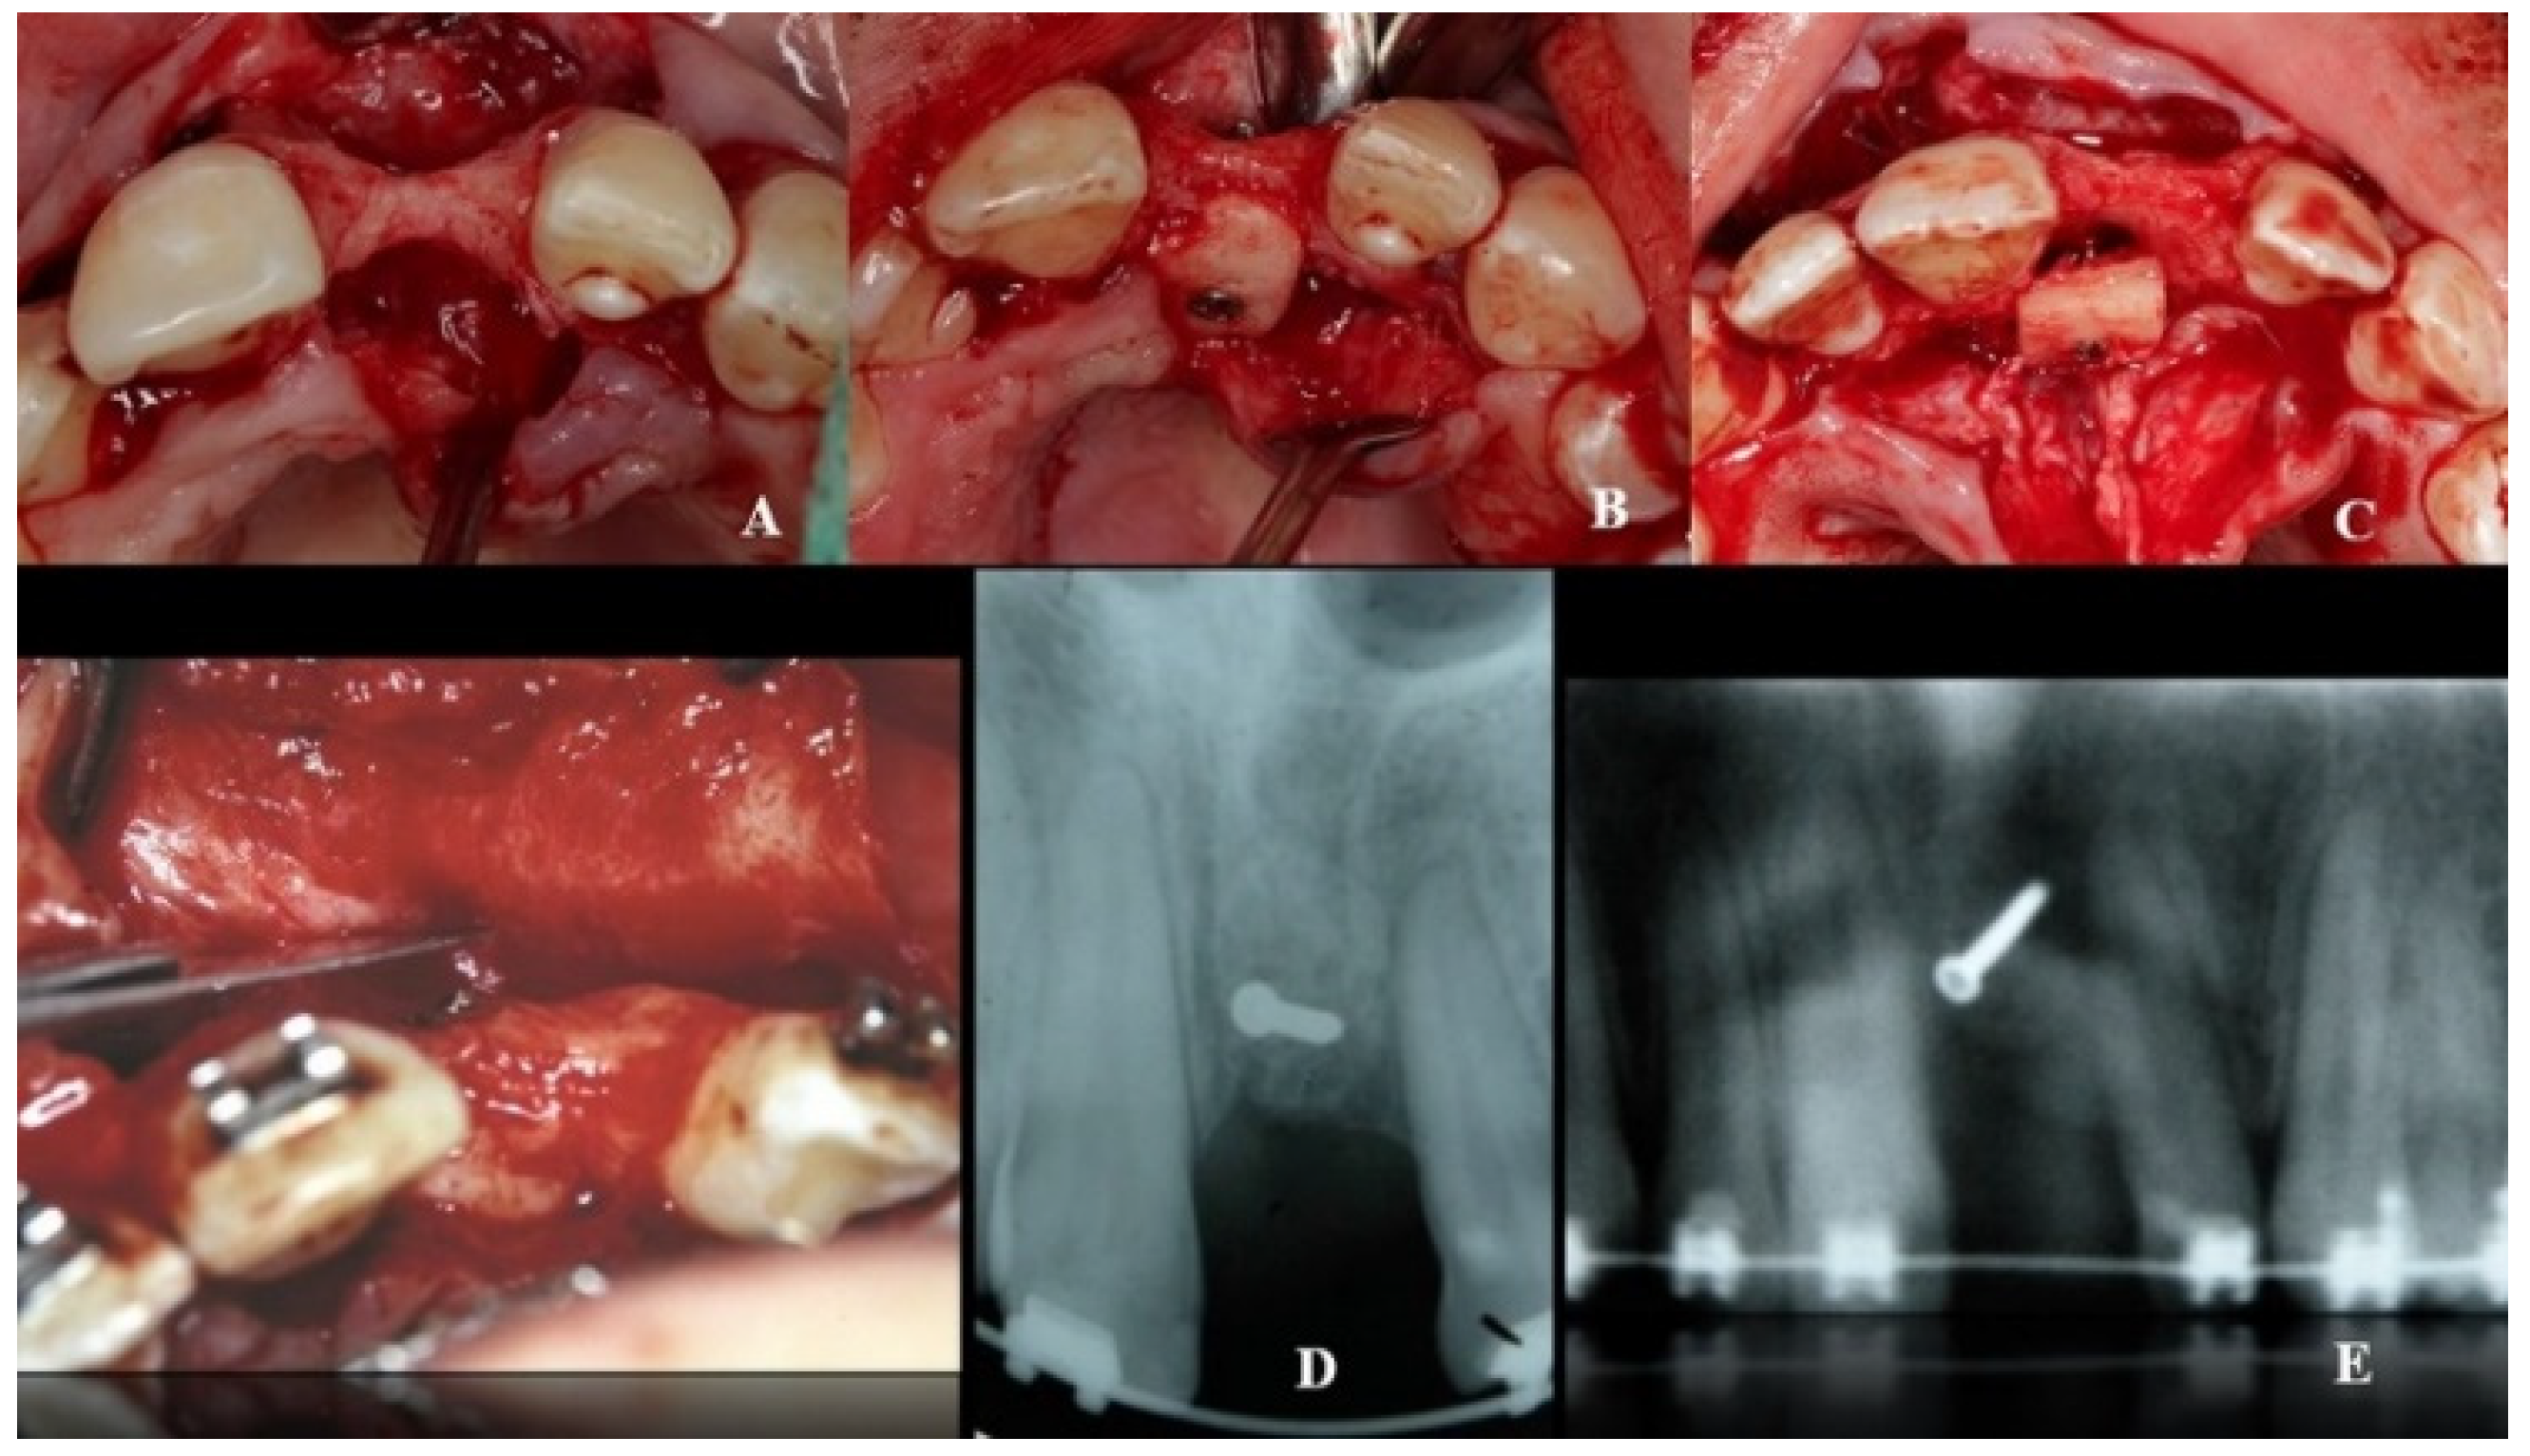

Axial sections corresponding to the middle part of the NPC showed the collapse of the vestibular plate and revealed the conduit’s size. All the cases presented thinning of the palatal ridge due to marked widening of the incisive foramen (Figure 2); so, according to the SAC Classification (i.e., simple, advanced, or complex), they were categorized as complex [2]. In addition, careful consideration had to be given to the nasopalatine bundle for correct three-dimensional positioning of the implant. Since the vertical and horizontal defects demanded bone augmentation before implant placement [17], a diagnostic wax-up was performed to determine the amount of bone needed in each case.

Figure 2.

Representative sections of a Cone Beam Computed Tomography (CBCT) scan in which the bone thickness of the maxillofacial region and the widening of the incisive foramen are observed. (A) Occlusal view. (B) Sagittal view.